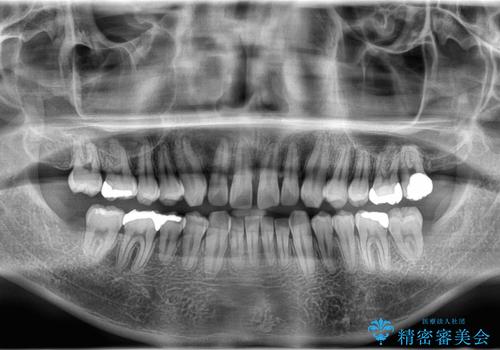

- 前歯の隙間と歯のデコボコを主訴にご来院された患者様です。

加えて、上下の奥歯が全く咬み合わないシザーズバイトの状態も認められました。

矯正検査の結果、非抜歯でインビザラインによる治療が可能と判断し、治療を行いました。

歯の隙間とデコボコ、シザーズバイトも改善され、咬み合わせや見た目が整い、患者様にも大変ご満足いただけました。